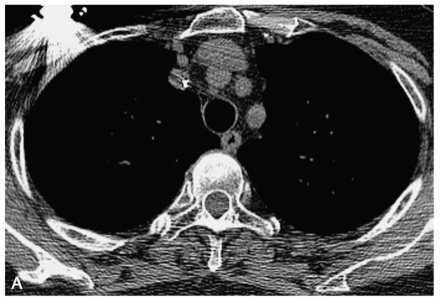

图1 胸部CT增强扫描

A.气管旁淋巴结肿大(白箭);B.沿双侧肺门向外周延伸的中央间质增生,支气管腔受压狭窄(白箭)